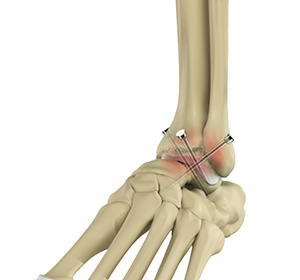

Ankle fusion, also known as ankle arthrodesis, is a surgical procedure commonly employed for the treatment of ankle arthritis in which the joint cartilage is severely damaged. The procedure involves fusion of the bones that form the ankle joint into one piece, which eliminates joint motion and relieves pain originating from the arthritic joint.

The ankle joint connects the leg to the foot and comprises three bones: the tibia, fibula, and talus. The tibia (shinbone) and fibula (calf bone) are the bones of the lower leg that articulate with the talus (ankle bone), enabling up-and-down movement of the foot. The joint surfaces of all these bones are lined by a thin, tough, flexible, and slippery surface called the articular cartilage, which acts as a shock absorber to cushion and reduce friction between the bones. The cartilage is lubricated by synovial fluid, which further enables smooth movement of the bones. Ligaments are tough, rope-like bands that connect bones to other bones, holding them in place to provide joint stability.

Ankle fusion surgery may be performed as an open surgery, where a large incision is made, or as a minimally invasive arthroscopic surgery, where small incisions are made to insert an arthroscope (a thin tube with a camera and light source) and miniature surgical tools. Open surgery is the commonly employed approach and involves the following steps:

- The joints are then fused together with the help of screws, wires, plates, or rods.